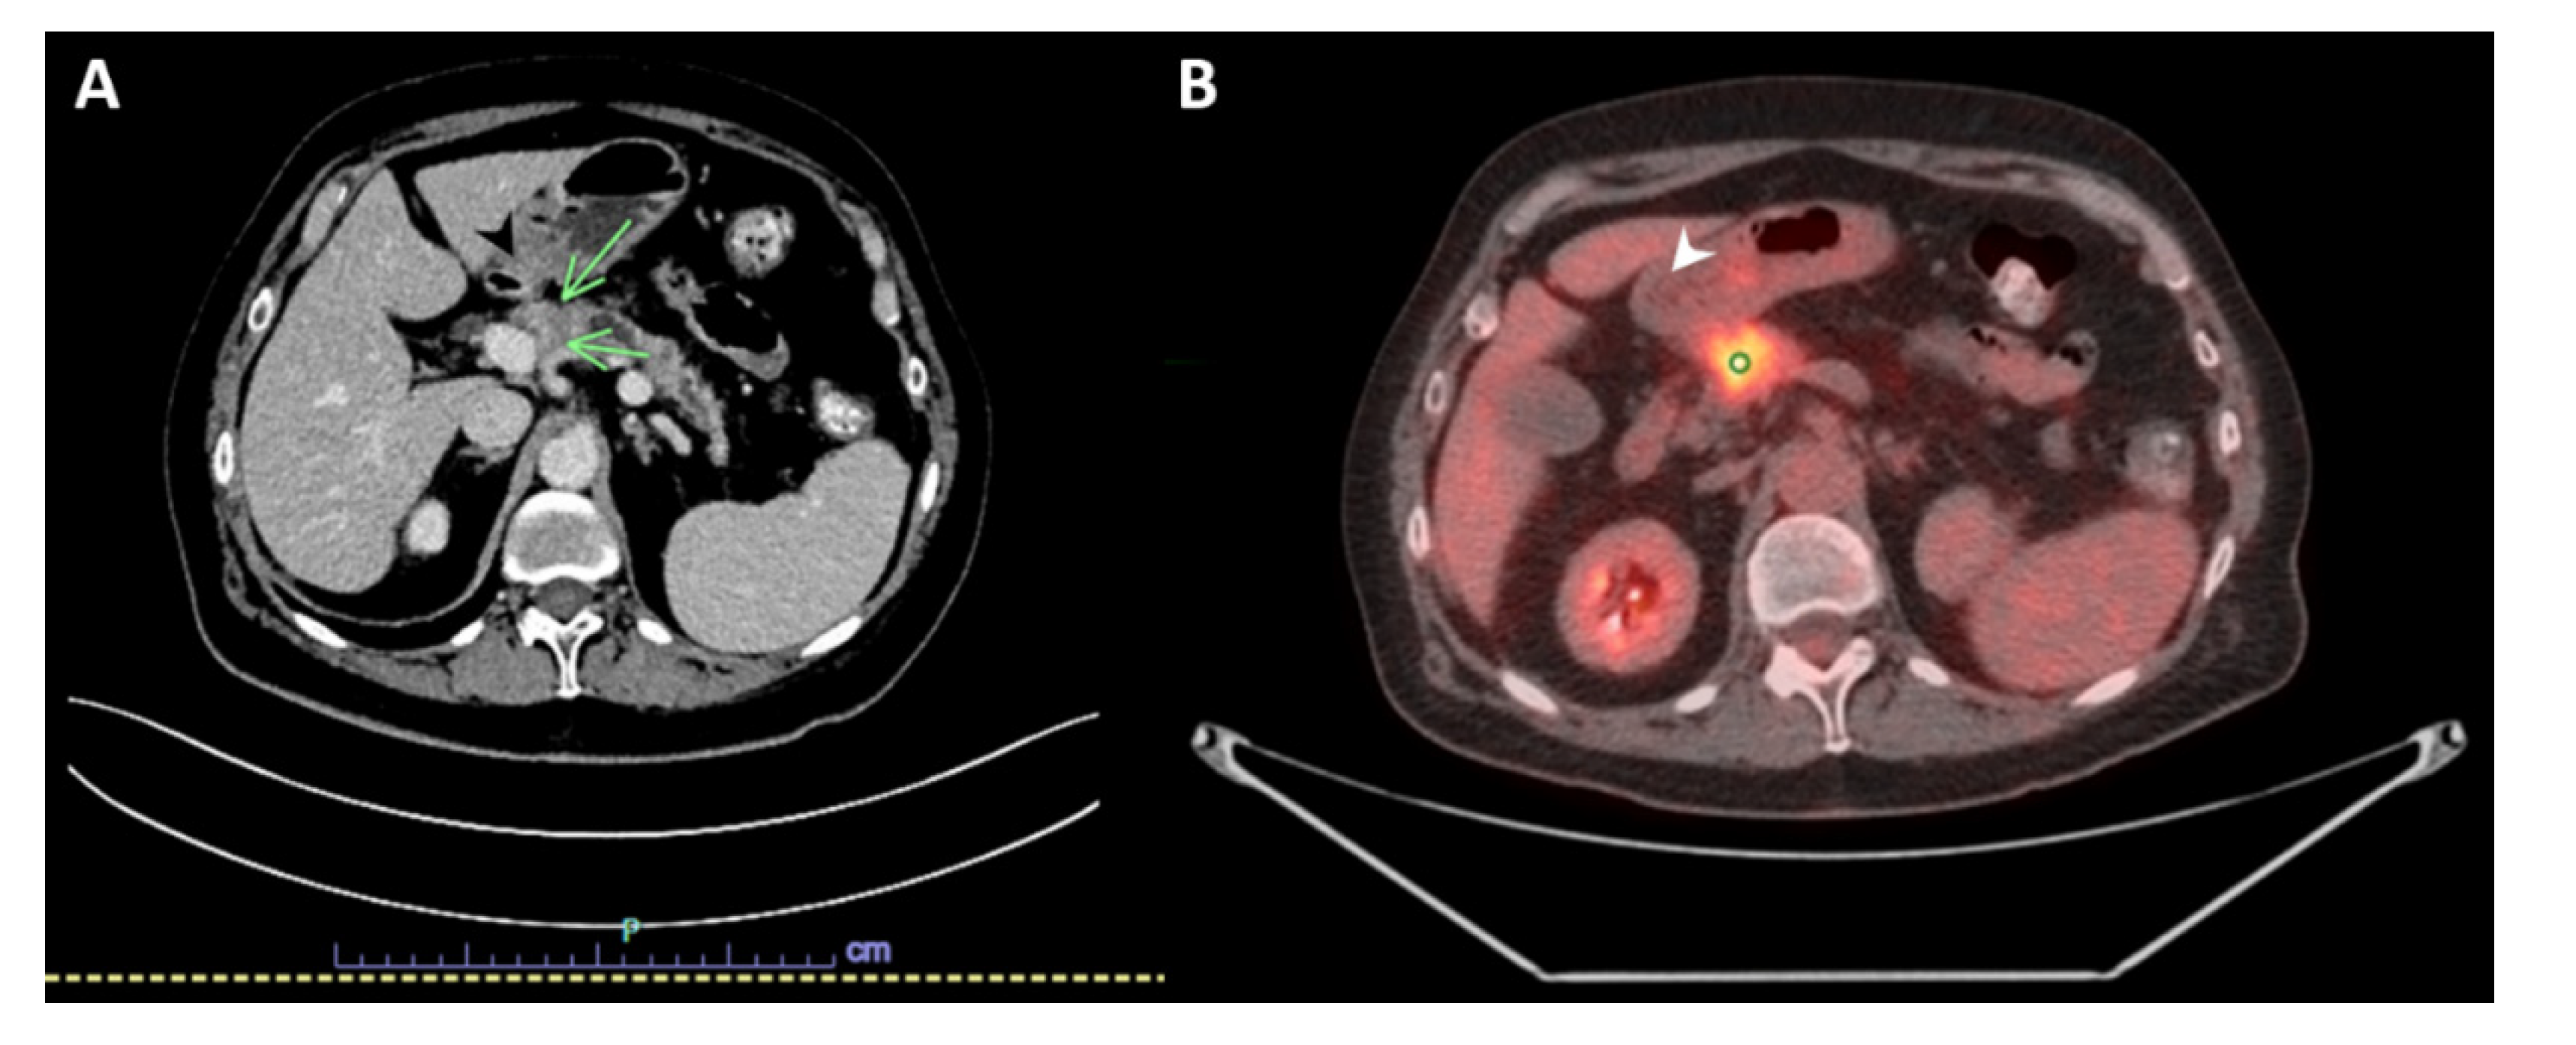

2. Case Presentation